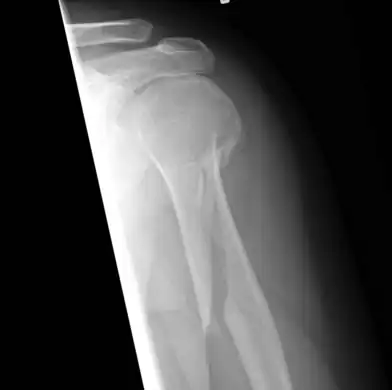

- An x-ray image of a spiral fracture to the left humerus of a 27-year-old male. The injury was sustained during a fall.